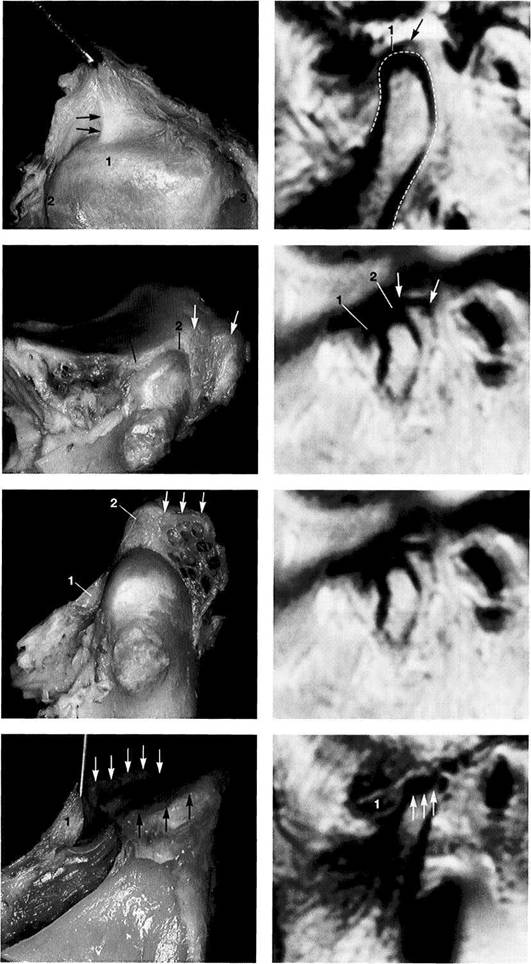

Normal joint

Left: Macroscopic anatomical pre­paration of a right temporo­mandibular joint with normal disk position. The pars posterior (1), pars anterior (2), pars media (arrow), and condyle (3) can be clearly seen.

Right: In spite of the reduction in signal caused by formalin fixation, the corresponding slice in MRI shows the identical relationships between the disk (1,2) and condyle

Medial disk displacement

Left: Formalin-fixed preparation from a right joint. In this anterosu-perior view, the displacement of the disk (arrows) toward the medial is evident.

Lateral pterygoid muscle

Lateral pole

Medial pole

Right: MRI in the angled coronal plane confirms the medial disk po­sition (arrows). The contours of the fossa and condyle are reproduced precisely.

Shape of the pars posterior

Left: Macroscopic anatomical pre­paration of a right articular disk showing its positional relationship to the condyle. The posteroinferior edge of the pars posterior (1) shows a small triangular area of fi­brosis (arrows).

Right: In spite of the sharply re­duced signal emission resulting from formalin fixation, even this type of change is accurately repro­duced (arrows). Here the use of a combination of T1 and T2 weight­ing is often helpful.

Reproduction of Anatomical Detail in MRI

Fibrosis of the bilaminar zone

Left: Formalin-fixed preparation of the centromedial part of a left tem­poromandibular joint with localized fibrosis of the bilaminar zone (ar­rows).

Pars posterior

Right: The MRI accurately repro­duces the abnormality (arrows) dis­tal to the flattened pars posterior. The contour of the condyle is indi­cated by a broken line.

Presumed "posterior disk displacement"

Left: Macroscopic preparation of a left temporomandibular joint with normal positioning of the pars an­terior (1) and pars posterior (2) in the lateral portion of the joint. The retrodiskal structures appear thick­ened.

Right: In an MRI there appears at first glance to be a posterior disk displacement (arrows). Under clos­er inspection, however, it can be seen that the pars anterior (1) and pars posterior (2) lie in correct rela­tion to the condyle.

Left: A view of the disk and the bil­aminar zone after further prepara­tion again reveals the correct posi­tional relationships. Here the pars anterior (1) and pars posterior (2) can be identified more readily. The presumed "posterior disk displace­ment" is a false positive interpreta­tion of the fibrosis of the bilaminar zone (arrows).

Right: MRI of the same joint shown in Figure 427.

Disk perforation and osteoarthrosis

Left: Anatomical preparation of a left temporomandibular joint with arthrotic changes (black arrows) and extensive disk perforation (white arrows). In the anterior re­gion only a part of the former pars anterior (1) can still be recognized.

Right: MRI shows similar conditions. The cortical layer of the arthrotic condyle is thickened extensively (arrows). The remainder of the pars anterior (1) can still be distin­guished.